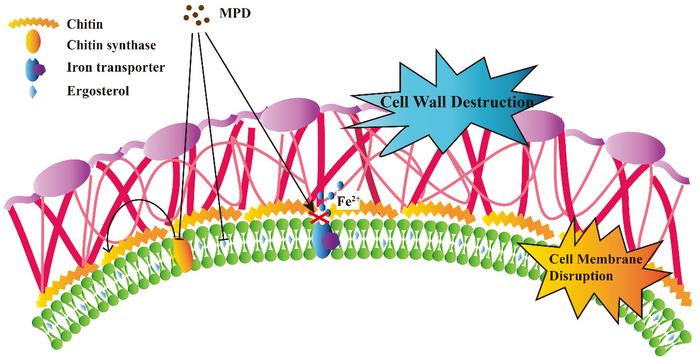

Subsequently, they analysed the safety of MPD, which has low toxicity to mammalian cell lines and is less likely to cause neurological damage and nephrotoxicity. The antifungal activity and safety of MPD supported further investigation of its antifungal mechanism.

They found that there may be an effect of MPD on the iron ion homeostasis of fungal cells by the fact that MPD was more sensitive to the wild-type Saccharomyces cerevisiae knockout strain (aft2Δ). MPD did reduce intracellular iron levels in Candida albicans cells, as analysed by iron ion probe staining.

The decrease in iron concentration leads to a decrease in the synthesis of ergosterol, an important component of fungal cell membranes, which results in increased permeability and reduced flow ordering of fungal cell membranes. In this case, along with the leakage of intracellular trehalose, the fungal cells eventually die. They also demonstrated the antifungal effect of MPD in vivo by using the Caenorhabditis elegans–Candida albicans infection model. The findings, therefore, demonstrate the efficacy of MPD as a novel antifungal compound, highlighting its potential as a promising option for the treatment of clinical candidiasis. The study also reveals the mechanism by which maleimide derivatives exert their antifungal effects.